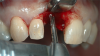

Fig 5. 1.5 mm of bone should surround the implant on either side.

Figure 5

Fig 6. The location for implant placement can then be established using a round bur.

Figure 6

A flap procedure reveals the bone, which should be wide enough to provide 1.5 mm of bone on either side of the implant (Figure 5).6 The amount and level of bone surrounding implants is important for osseointegration, esthetics, and long-term survival.6 The location for implant placement can then be established using a round bur to place a mark in the center of the crest of bone from mesial-distally and facial-palatally (Figure 6).